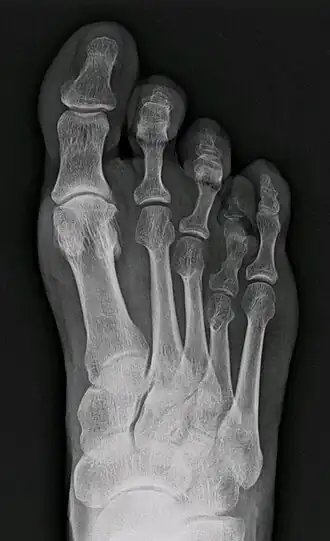

| Raio-x de um caso de braquimetatarsia envolvendo o quarto osso do metatarso. | |

Braquimetatarsia (do grego brachys, que se traduz por «curto», e metatarsia, relativo ao metatarso) é uma rara condição congênita causada pelo fechamento prematuro da epífise, o que torna um dos cinco ossos longos do pé (o metatarso) anormalmente curto, resultando em um dedo menor e mais elevado que os outros.[1][2][3][4] Tal anomalia é também conhecida nos meios científicos como «metatarso curto congênito».[3]

A braquimetatarsia é uma condição genética rara, cuja ocorrência é vinte e cinco vezes mais comum em mulheres que em homens, normalmente em ambos os pés (bilateralmente) e no quarto dedo.[2] Normalmente só se torna visível a partir dos quatro anos, com o fechamento paulatino das placas ósseas.[2][3]